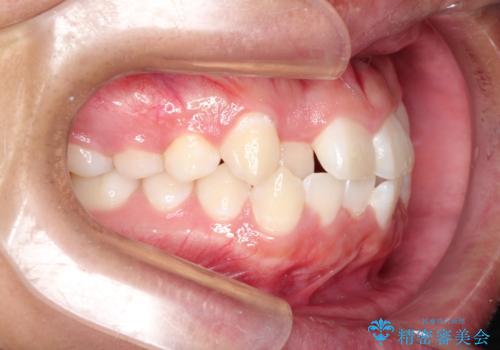

前歯のガタガタを目立たずきれいにしたい インビザラインによる見えない矯正

- 前歯のがたつきを主訴に来院されました。

上顎の前から2番目の歯の噛み合わせが反対になっていました。

抜歯矯正も考えられるケースでしたが、非抜歯での矯正を希望され、インビザラインにて治療することとなりました。

目立たずに矯正を終えることができ、患者様にも満足していただきました。